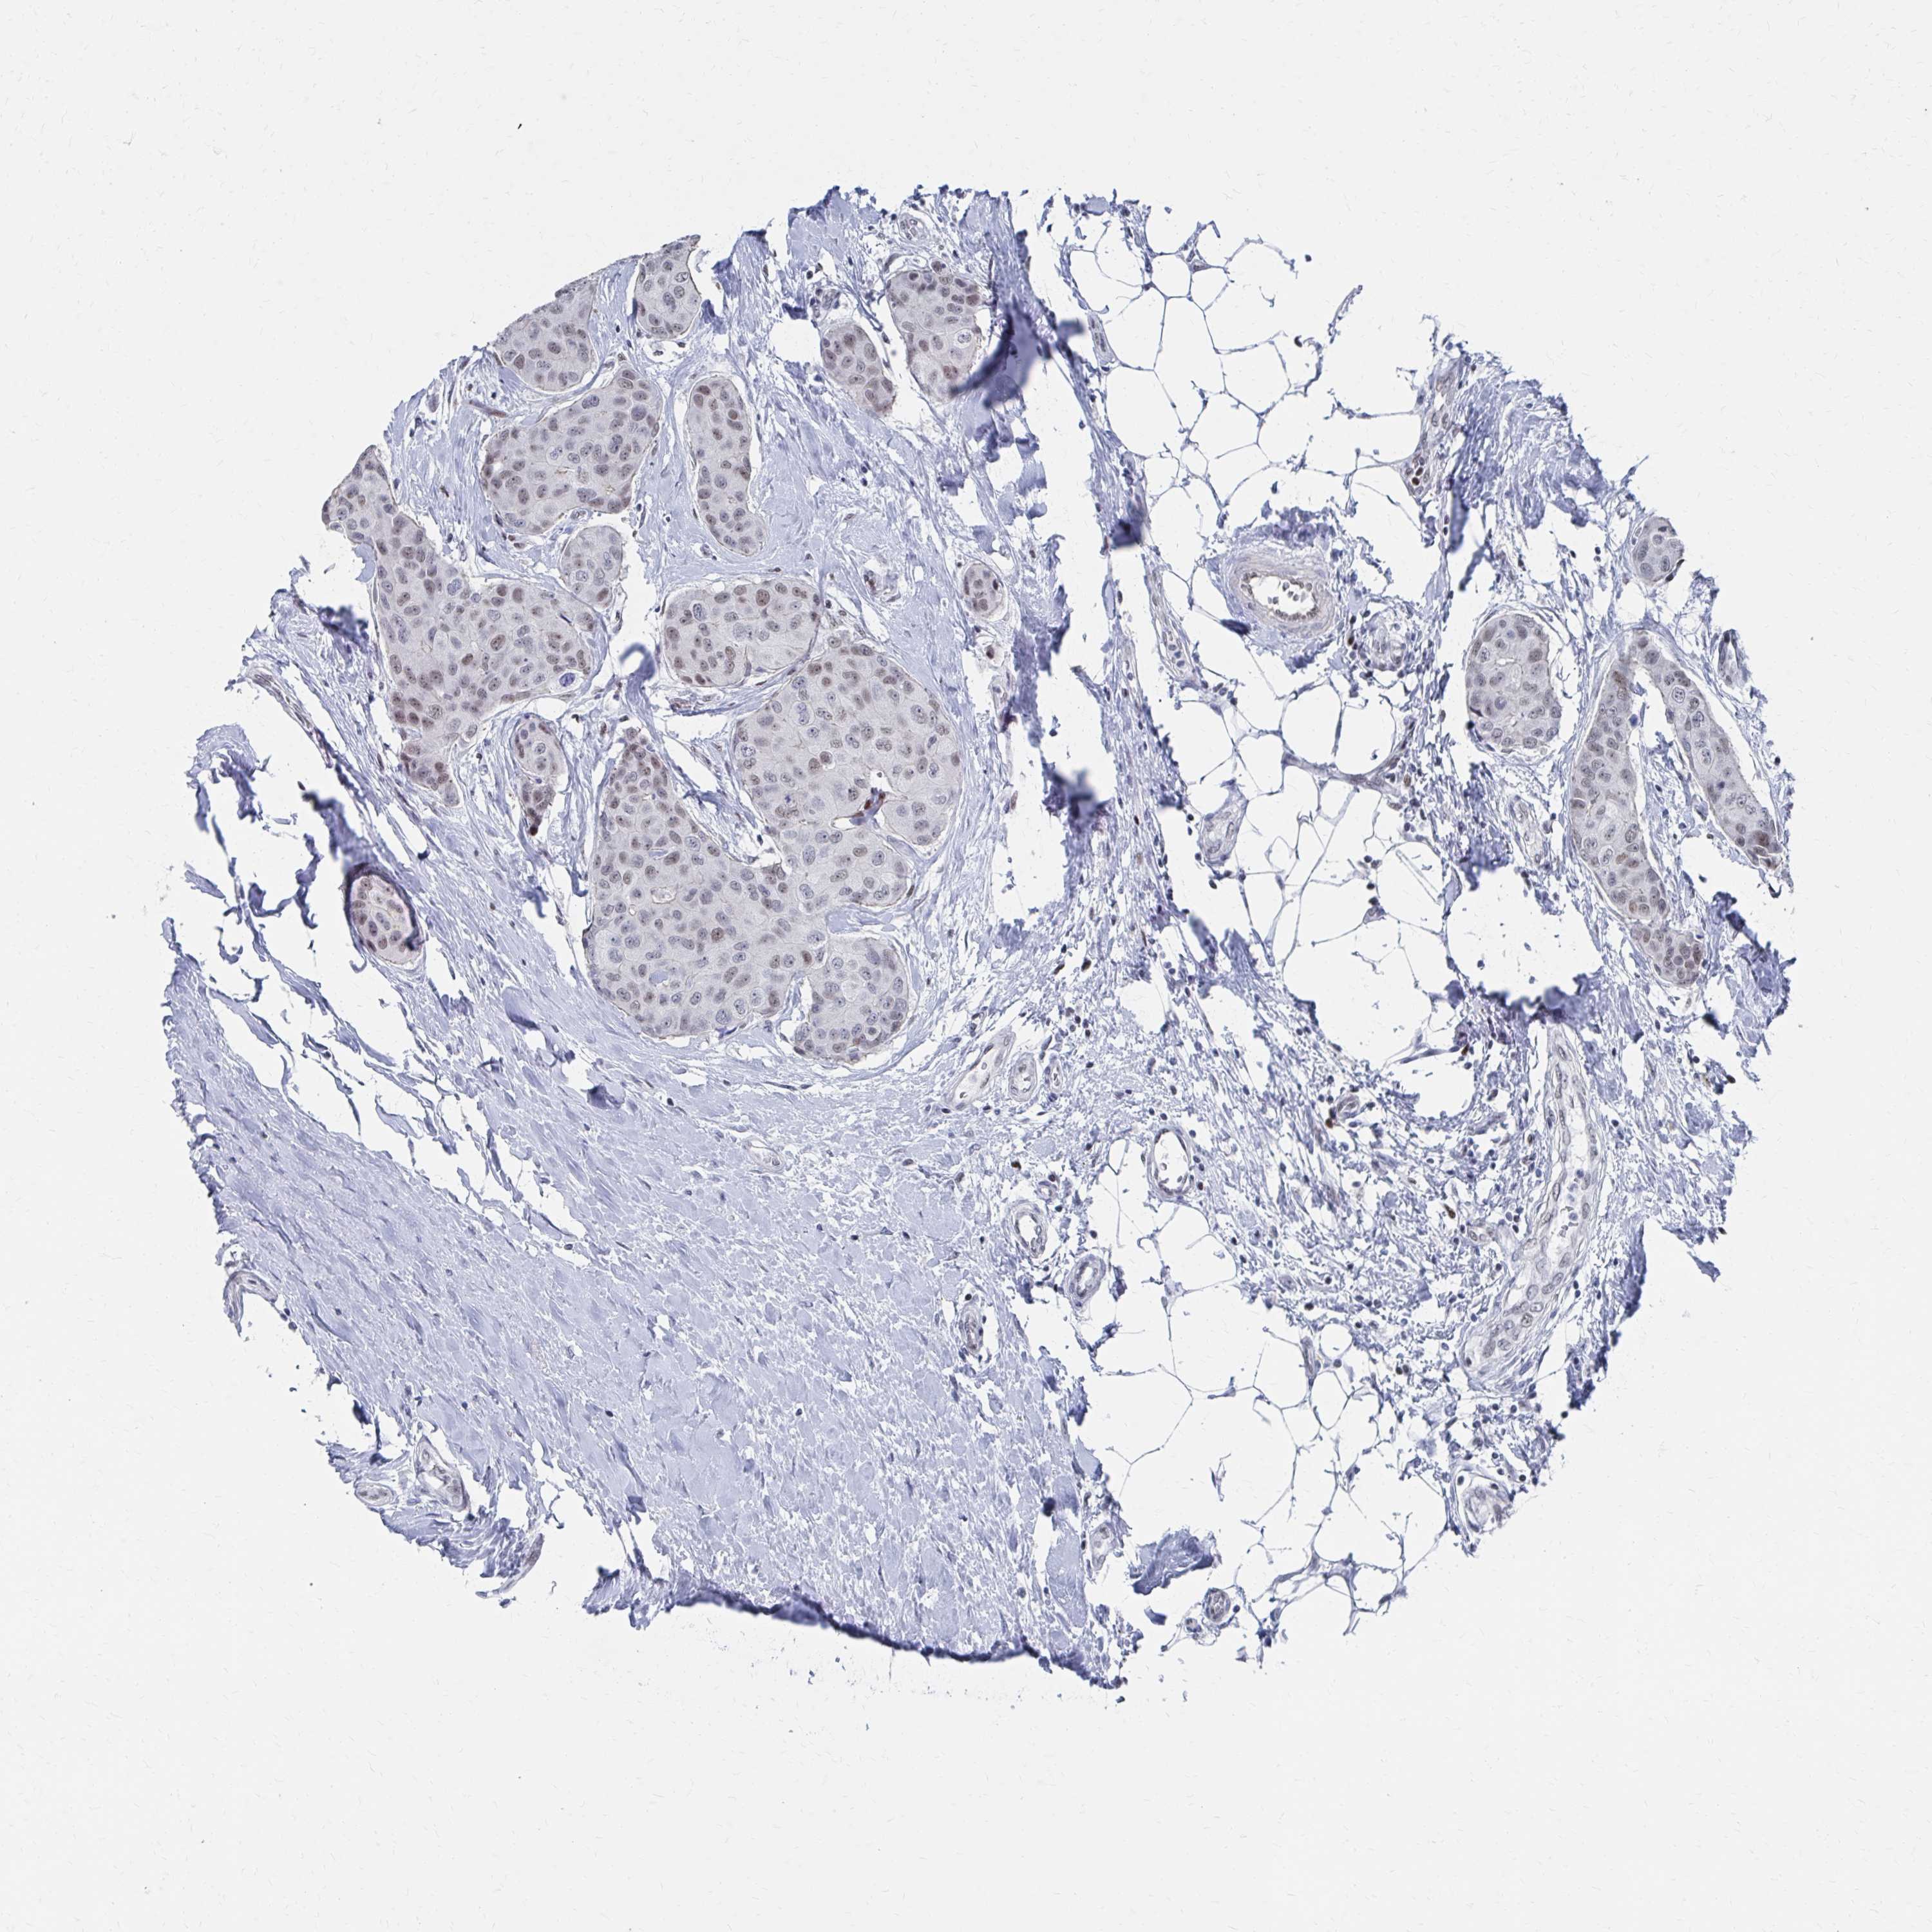

CANCER BREAST CANCER Show tissue menu

BRCA TCGA BRCA VALIDATION PROTEIN EXPRESSION

ANTIBODIES

AND

VALIDATION